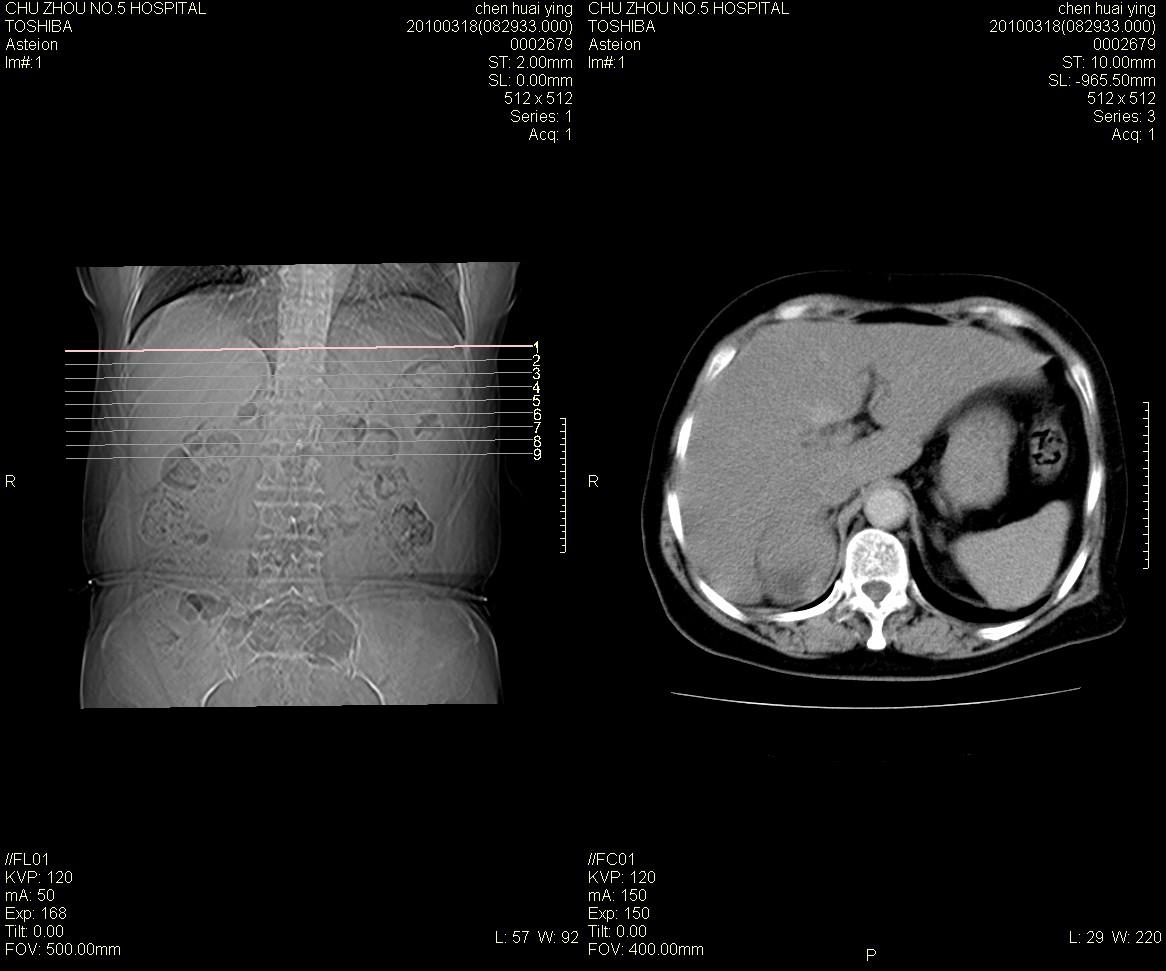

标题: CT25148 肾上腺增强

ct25148增强图片

动脉期太早了,扫的有点低。考虑良性占位右侧肾上腺嗜铬细胞瘤并坏死囊变可能性大,神经鞘瘤不排除。

右侧肾上腺占位性病变,病人是否有高血压?嗜铬细胞瘤?

右侧肾上腺嗜铬细胞瘤并坏死囊变可能性大